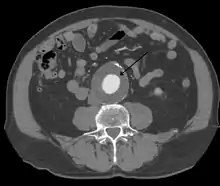

The diagnosis of an abdominal aortic aneurysm can be confirmed by the use of ultrasound. Rupture may be indicated by the presence of free fluid in the abdomen. A contrast-enhanced abdominal CT scan is the best test to diagnose an AAA and guide treatment options.[10]

Abdominal aortic aneurysm

Abdominal aortic aneurysms (AAAs) are more common than their thoracic counterpart. One reason for this is that elastin, the principal load-bearing protein present in the wall of the aorta, is reduced in the abdominal aorta as compared to the thoracic aorta. Another is that the abdominal aorta does not possess vasa vasorum, the nutrient-supplying blood vessels within the wall of the aorta. Most AAA are true aneurysms that involve all three layers (tunica intima, tunica media and tunica adventitia). The prevalence of AAAs increases with age, with an average age of 65–70 at the time of diagnosis. AAAs have been attributed to atherosclerosis, though other factors are involved in their formation.[7]

The risk of rupture of an AAA is related to its diameter; once the aneurysm reaches about 5 cm, the yearly risk of rupture may exceed the risks of surgical repair for an average-risk patient. Rupture risk is also related to shape; so-called "fusiform" (long) aneurysms are considered less rupture-prone than "saccular" (shorter, bulbous) aneurysms, the latter having more wall tension in a particular location in the aneurysm wall.[9]

Before rupture, an AAA may present as a large, pulsatile mass above the umbilicus. A bruit may be heard from the turbulent flow in the aneurysm. Rupture may be the first sign of AAA. Once an aneurysm has ruptured, it presents with classic symptoms of abdominal pain which is severe, constant, and radiating to the back.[9]